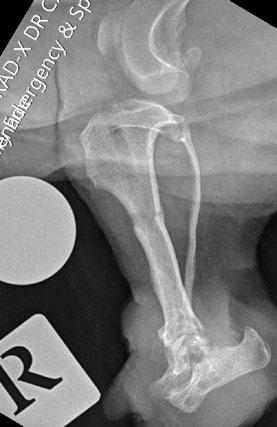

Osseointegrated Transcutaneous Amputation Prostheses in Veterinary Medicine

Daniel R James